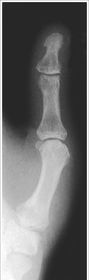

| What's the evaluation criteria for the PA Finger X-Ray? | ANATOMY: distal phalynx -> distal 1/2 of metacarpal demonstrated CRITERIA: - equal concavity on both sides of phalanges - IP and MCP open - no overlapping of adjacent fingers POSITIONING: CR perpendicular @ PIP joint |

| What's the evaluation criteria for the Lateral finger x-ray? | ANATOMY: entire digit demonstrated CRITERIA: open joint spaces concave to one side, while the dorsal side is straight no overlapping of adjacent fingers/soft tissues POSITIONING: CR perpendicular @ PIP joint |

| Oblique finger x-ray image criteria? | ANATOMY: entire digit demonstrated CRITERIA: more concavity to one side open joint spaces no superimposition of adjacent fingers POSITIONING: CR perpendicular @ PIP joint |